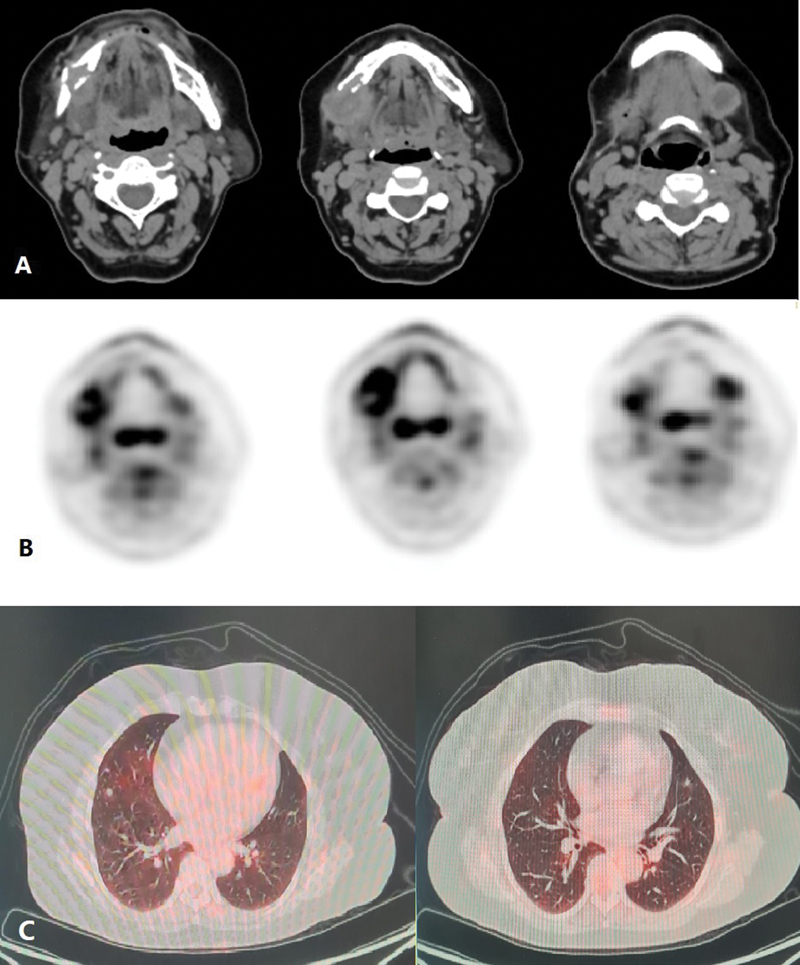

A 56-year-old lady, with no comorbidities and no habits presented with right submandibular swelling which gradually increased over 2 years. On clinical examination, the submandibular mass was lobulated and soft in consistency measuring 3 × 4 cm and not fixed to the overlying skin. There were no signs of inflammation and the swelling was not tender to touch. There was a palpable left level Ib neck node of 1.5 × 2 cm in size in the contralateral neck. The rest of the head and neck area examination was noncontributory. Computed tomography (CT) imaging ([Fig. 1A]) done was suggestive of a 28 × 27 × 39 mm sized ill-defined soft tissue lesion seen in the hemimandible along the right lower alveolus which was causing destructive cortical erosion. The adjacent enhancing soft tissue component showed loss of fat planes with the right submandibular gland inferiorly. A peripherally enhancing centrally necrotic left submandibular lymphadenopathy was present measuring 18 × 17 mm in size. Whole-body positron emission tomography-CT (PET-CT) scan done was suggestive of 3 × 2.4 cm sized fluorodeoxyglucose (FDG) avid spiculated lesion in the right submandibular region, eroding overlying angle and adjacent posterior body of the right hemimandible and infiltrating the right anterior belly of the digastric and closely abutting platysma. A 1.7 × 2.2 cm sized FDG avid left cervical level Ib lymph node was also noted. Heterogeneously, FDG avid discrete cervical level Ia and bilateral level II lymph nodes were also present. Mild FDG avid multiple subpleural and parenchymal nodules were noted in bilateral lung fields suggestive of metastasis ([Fig. 1C]). Biopsy from the right submandibular region was suggestive of EHE. In view of rare disease and asymptomatic suspicious lung metastasis, the case was discussed in a multidisciplinary tumor board following which the patient was taken up for wide local excision with right segmental mandibulectomy with bilateral supraomohyoid neck dissection. Histopathology of the resected specimen was suggestive of EHE involving the right submandibular gland and underlying bone ([Fig. 2A]) with maximum tumor size of 2.8 cm, medial and lateral soft tissue margins were involved by the tumor, perineural invasion was present ([Fig. 2B]), and lymphovascular invasion was not seen. Federation Nationale des Centres de Lutte Contre Le Cancer (FNCLCC) grade 4, mitotic rate was < 1/50 high-power field (HPF), and necrosis 10%. ([Fig. 2C]). One lymph node in the left level Ib was positive (out of 5), while the right-sided nodes were negative. Tumor cells were immunoreactive for CD34 ([Fig. 2D]). In view of positive margin and lymph node involvement, the patient was planned for adjuvant radiation to a dose of 60 Gy in 30 fractions to postoperative bed and involved the lymph node region by image-guided external beam radiotherapy (RT) technique. In phase 1, 50 Gy in 25 fractions was delivered to the tumor bed and bilateral neck region, and in phase 2 (boost), 10 Gy in 5 fractions was delivered to the tumor bed and involved the nodal region, Therefore, a total of 60 Gy in 30 fractions, 2 Gy per fraction, one fraction daily, over 6 weeks along with cisplatin chemotherapy (40 mg/m2) concurrently was given once a week, which she tolerated well with grade 1 dermatitis and grade 2 mucositis. The patient recovered from acute toxicities 2 weeks after completion of RT and was started on targeted therapy tablet pazopanib (dose 400 mg) twice a day to control systemic disease and reduce the risk of locoregional failure. PET-CT scan repeated after 3 months was suggestive of postoperative fibrosis of the right submandibular region with stable pulmonary metastasis. At 2-year follow-up, the patient is asymptomatic and on tablet pazopanib dose reduced to 200 mg twice a day due to oral mucositis. Latest PET-CT showed local-regional control and metabolically inactive pulmonary metastatic diseases.

Fig 1: Contrast-enhanced computed tomography (CT) (A) and positron emission tomography (PET) images (B) showing soft tissue lesion seen in the right hemimandible causing cortical erosion and involving the submandibular gland inferiorly with an enhancing centrally necrotic left submandibular lymphadenopathy and (C) mild fluorodeoxyglucose (FDG) avid multiple parenchymal nodules were noted in bilateral lung fields suggestive of metastasis.